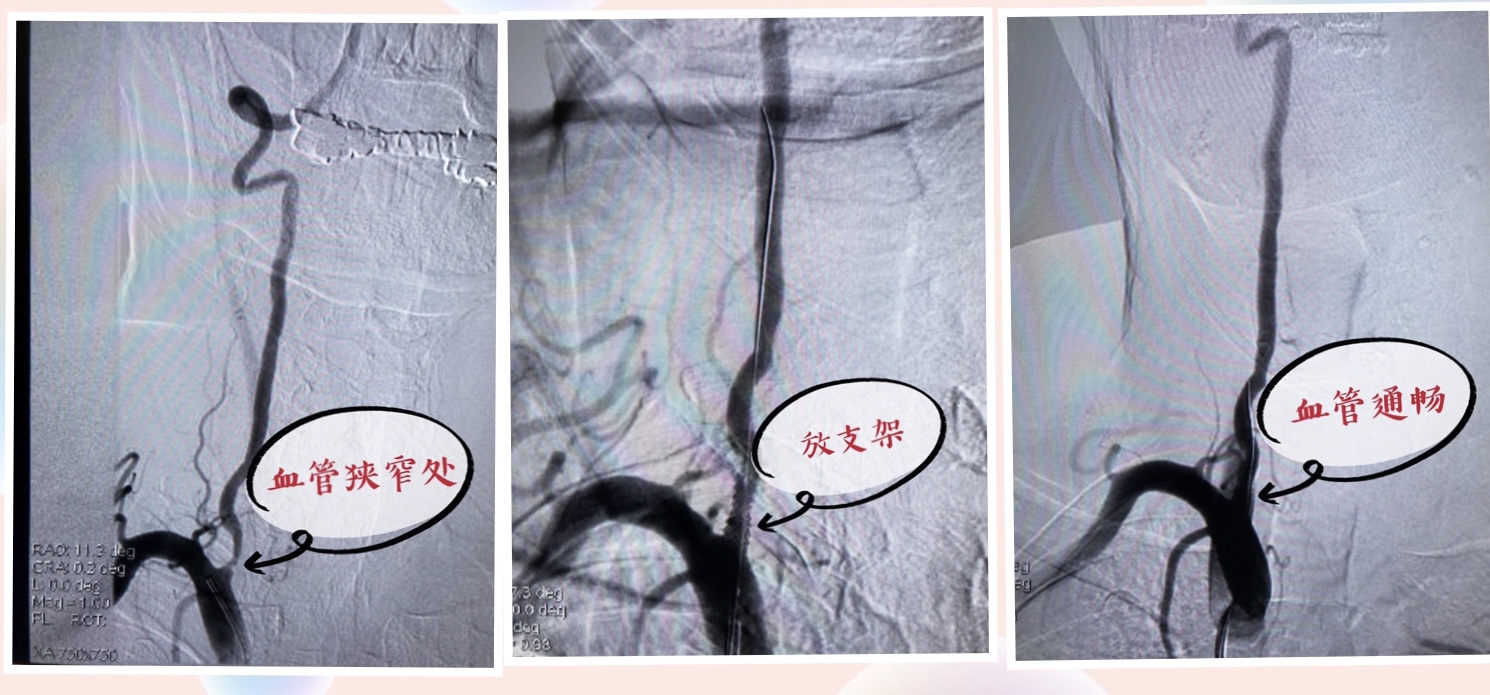

颈动脉狭窄是脑梗死的常见发病原因。颈动脉内膜剥脱术和颈动脉支架成形术是治疗颈动脉狭窄,恢复血流的有效手段。对于存在血管狭窄的病人,医生会根据病情给予药物治疗或者手术治疗的建议,当然手术后还要长期服药。

下面这张图片是我们科室一个病人进行支架成形术的造影图。